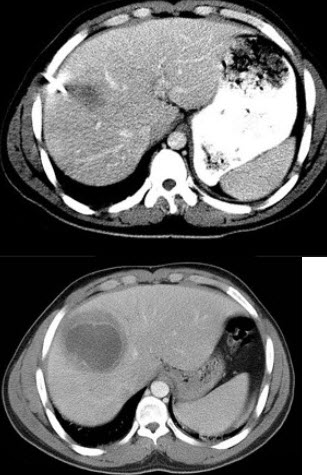

90、单项选择题

下列图像最佳诊断是什么()

A.阿米巴肝脓肿

B.原发性肝癌

C.肝转移瘤

D.肝硬化

E.脂肪肝